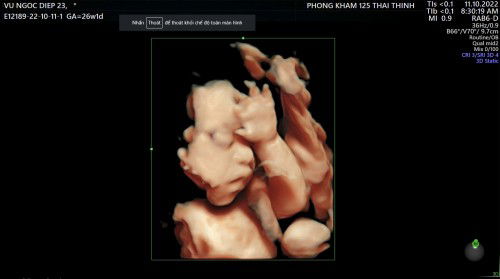

Có khi nào siêu âm sai lệch nhiều k các mẹ ơi 😀😀 36w 2kg5 - sau 1 tuần bé lên có 1 lạng-mẹ k tăng kí luôn ạ 😅😅 E bé 37w nhà em siêu âm có 2kg6 - buồn thối ruột Trong khi con mẹ ăn trứng lộn - đầu tư uống matilia , sữa tươi k đường đều đặn . Nhau thì vẫn độ 0-1 , chả hiểu sao lại k vào con Thế đổ đi đâu hết ạ 😭😭 sốt hết cả ruột Đứa đầu nhà em cũng tầm này sắp đẻ siêu âm bsi bảo có 2kg2 , thế mà đẻ 3kg4 nhưng cách đây 5 năm rồi ... giờ máy móc tiên tiến hơn trước có khi nào vẫn sai lệch nhiều k các mẹ nhỉ 🫥🫥🫥 #Xin_cac_mom_chi_bao #cho_em_xin_ý_kiến_với_ạ #bầu_lần_2